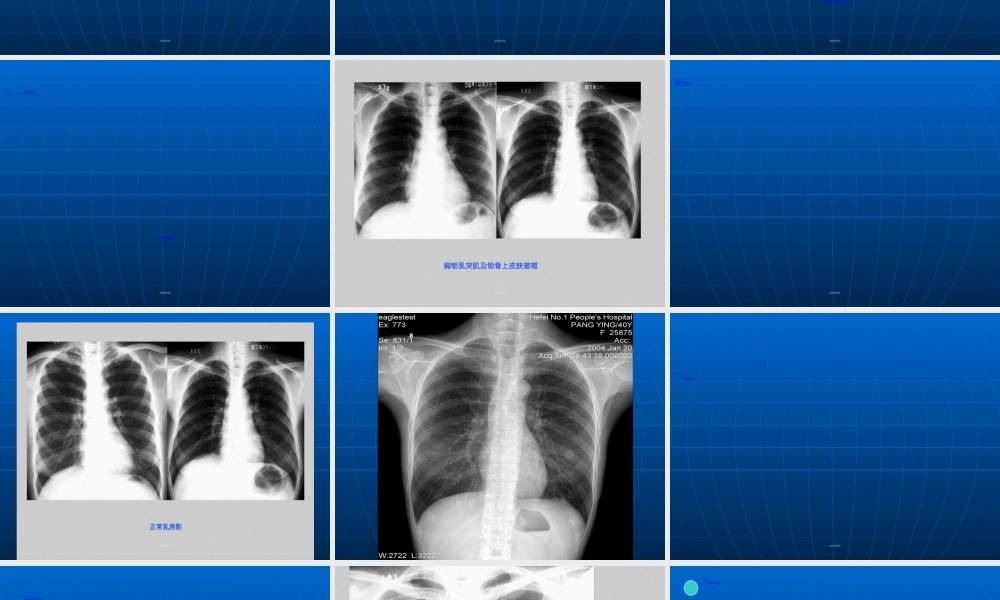

当X线穿过胸部时,由于两肺与其周围的胸壁、纵隔及横膈对X线吸收的差别,产生天然(tiānrán)对比影像,因此呼吸系统疾病应用X线检查较其他系统普遍。近年来,由于CT、MRI、DSA的临床应用,突破了普通X线诊断的限度。但普通X线检查在胸部疾病诊断中仍占主导地位。第第第第第第第第第第1.常规X线检查(jiǎnchá):(1)透视:首选(2)摄片:a.胸部正位片:后前位、前后位;立位、卧位b.胸部侧位片:左侧位、右侧位c.胸部斜位片:左前斜、右前斜d.前弓位片:显示肺尖及锁骨肋骨后方重叠的病变,中叶或舌叶不张,叶间胸膜积液。第第第第第第第第第第由于CT及MRI的应用,X线的一些如体层摄影,高千伏摄影,支气管造影检查已逐步淘汰(táotài),仅属于介入放射学范畴的肺动脉造影,支气管造影及经皮肺穿刺仍经常使用。第第第第第第第第第第2.CT检查:胸部CT扫描较普通X线检查的优越性:⑴密度分辨率高;⑵CT断面无影像重叠,病灶显示清晰;⑶适用于普通胸片表现正常,而临床高度怀疑胸、肺部病变。CT扫描一般用平扫,在需要观察病变与肺门、纵隔血管的关系(guānxì)时,及纵隔有无淋巴结转移时需增强扫描。第第第第第第第第第第3.MRI检查:对纵隔心大血管及胸壁病变有着(yǒuzhe)独特的优点,对肺实质病变效果较差。第第第第第第第第第第第第第第第第第第第第(zhèngcháng)正常胸部X线影像(yǐnɡxiànɡ)是胸腔内、外各种组织和器官的影像(yǐnɡxiànɡ)重叠,熟悉各种影像(yǐnɡxiànɡ)的正常及变异,是胸部影像(yǐnɡxiànɡ)诊断的基础。第第第第第第第第第第(xiōngkuò)包括软组织和骨骼,正常两侧对称。一、胸壁软组织:1.胸锁乳头肌及锁骨上皮肤皱褶:(1)胸锁乳头肌起自胸骨柄及锁骨胸骨端,斜向后止于乳突,在两肺尖内侧形成外缘锐利(ruìlì)、均匀致密的图像。(2)锁骨上皮肤皱褶系锁骨上皮肤及皮下组织的投照。表现为与锁骨上缘平行的3~5mm宽的薄层软组织影,其内侧与锁骨乳头肌影相连。略成直角。当肥胖者锁骨上窝不凹陷,或有肿块时不显影。第第第第第第第第第第第第第第第第第第第第2.胸大肌:于两侧肺野中外带可形成扇形致密影,下缘锐利,呈一斜线与腋前皮肤皱褶连续。一般右侧较明显,不可误认为病变。3.女性(nǚxìng)乳房及乳头:女性乳房可在两肺下野形成下缘清楚、上缘不清且密度逐渐变淡的半圆形致密影,其下缘向外与腋部皮肤连续,勿误认为肺炎。乳头在两肺下野相当与第5前肋间处,有时可形成小圆形致密影...